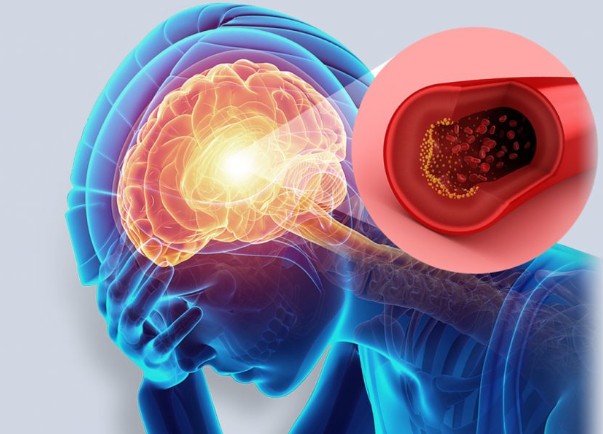

위의 증상들이 **짧게 나타났다가 사라지는 경우(TIA, 일과성 허혈 발작)**가 있습니다.

이 경우 “지나갔으니 괜찮다”고 넘기면 안 되고,

48시간~일주일 내에 본격적인 뇌졸중이 올 수 있으니 즉시 병원 진료가 필요합니다.

- 전조증상이 하나라도 보이면 즉시 119 또는 응급실 내원이 가장 중요합니다.

- 시간이 생명입니다.

뇌졸중 치료의 황금 시간대는 증상 발생 후 3시간 이내입니다. - 미니중풍(TIA)도 반드시 검진을 받아야 하며,

고혈압, 당뇨, 고지혈증, 흡연, 비만, 스트레스는 주요 위험요소입니다.

뇌졸중은 단 1분의 대응 차이로 생명과 후유증을 가를 수 있는 질환입니다.